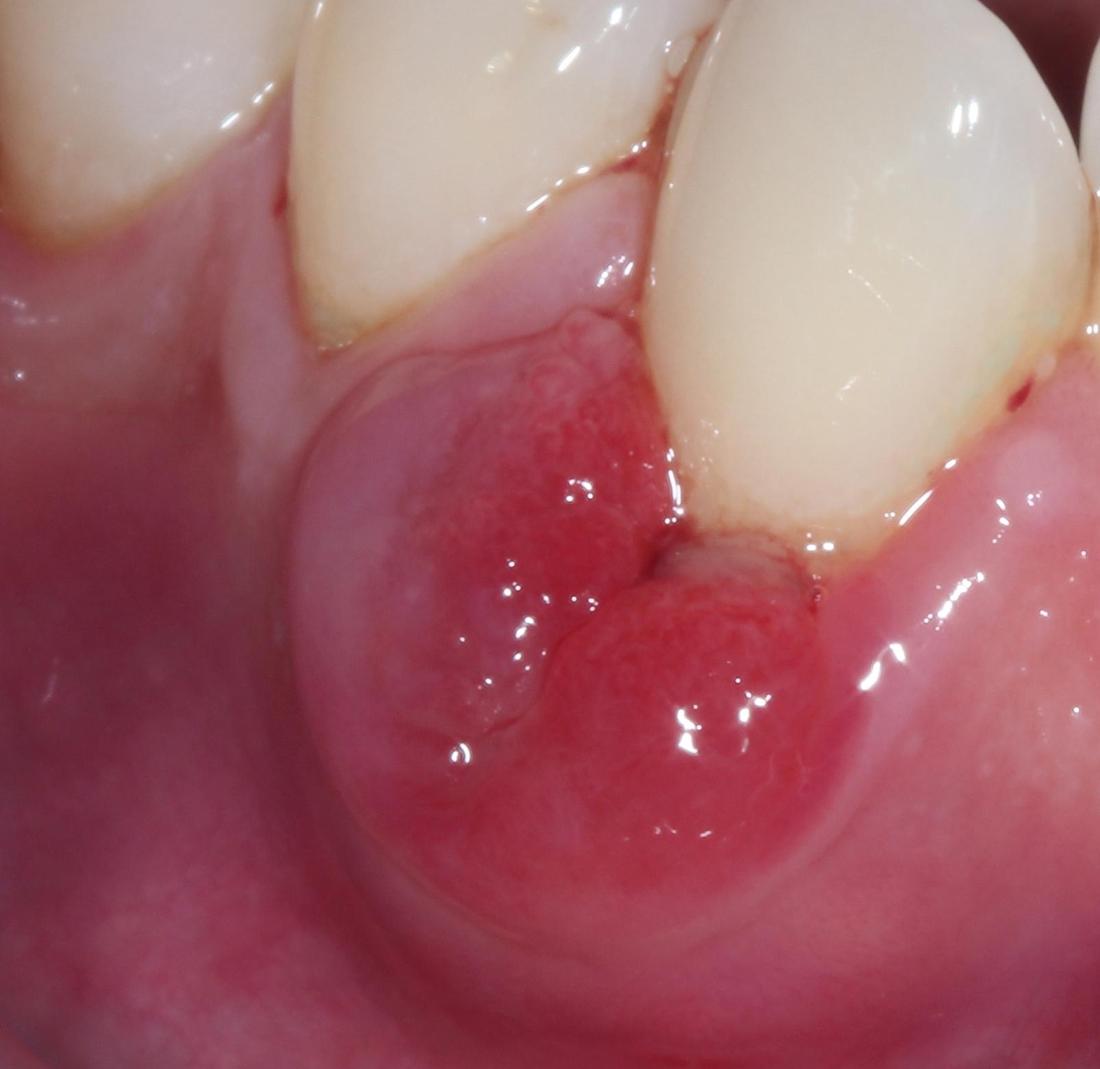

Before: Patient reported swollen gums around tooth #27.